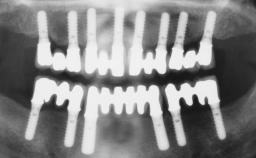

Immediate Loading of Six Implants in the Mandible and Six Implants in the Maxilla and Final Restoration with Full-Arch CAD/CAM Metal Framework FDPs Involving Digital Planning and Guided Surgery

# of Implants 12

Type of Implants One-Piece